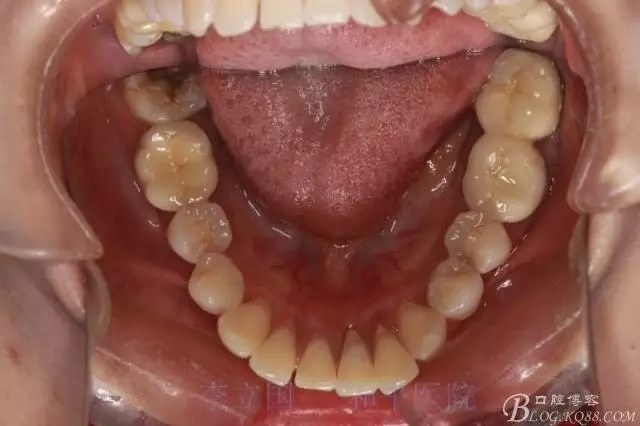

1.拔除14、24、31。

1.患者上前牙直立,面型前突,典型的嘴凸牙不吐,關(guān)鍵是前牙轉(zhuǎn)矩控制,建議使用高轉(zhuǎn)矩托槽。

2.磨牙關(guān)系一側(cè)完全遠(yuǎn)中,一側(cè)遠(yuǎn)中尖対尖,采用兩個(gè)上4,一個(gè)下1的拔牙模式。

5.回收過程中,上下前牙輕搖椅,防止覆合加深。